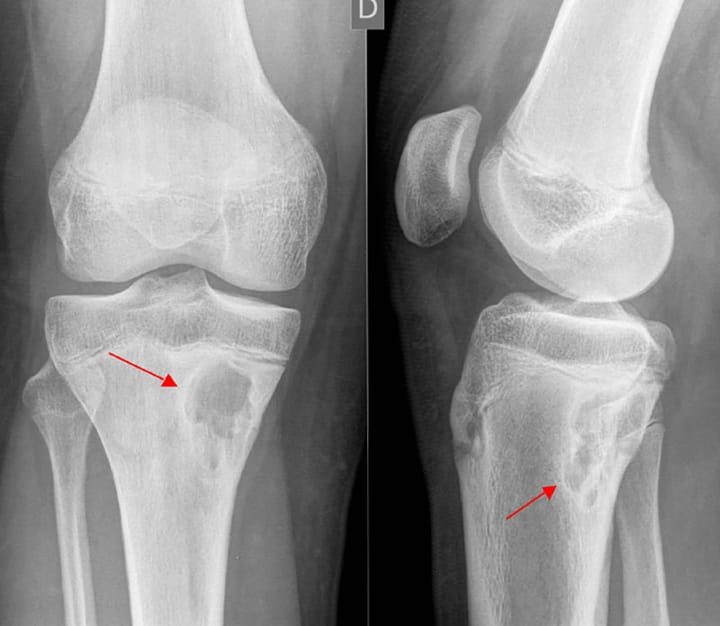

Échographie L'échographie musculo-squelettique du membre inférieur : sémiologie et applications échographiques en présence d'un syndrome fémoro-patellaire